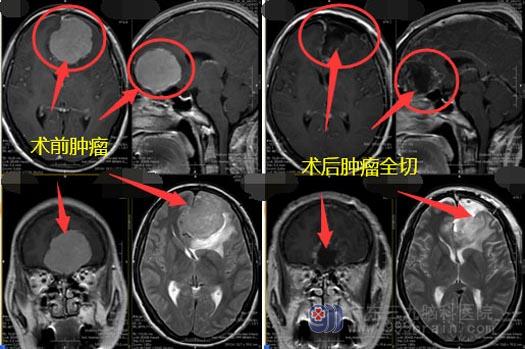

医院副院长、神经外五科主任鲁明带领医生团队,于2019年12月30日在全麻下经冠状切口左侧额部行双侧额部巨大脑膜瘤切除术。术中显微镜下全切肿瘤,手术过程顺利。术后复查头颅MR:原双侧额部大脑镰旁巨大脑膜瘤已切除;术后病理:脑膜瘤 WHO I级。